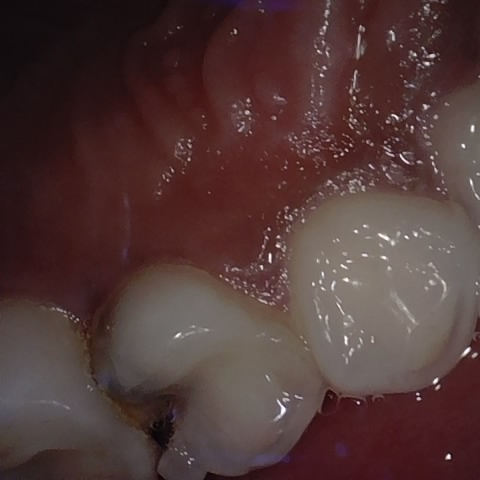

Incorrect Quality Level

The reference annotation for this image is

None

.

Please select the correct quality level.

Image 142 / 1103

Annotated as "Good"